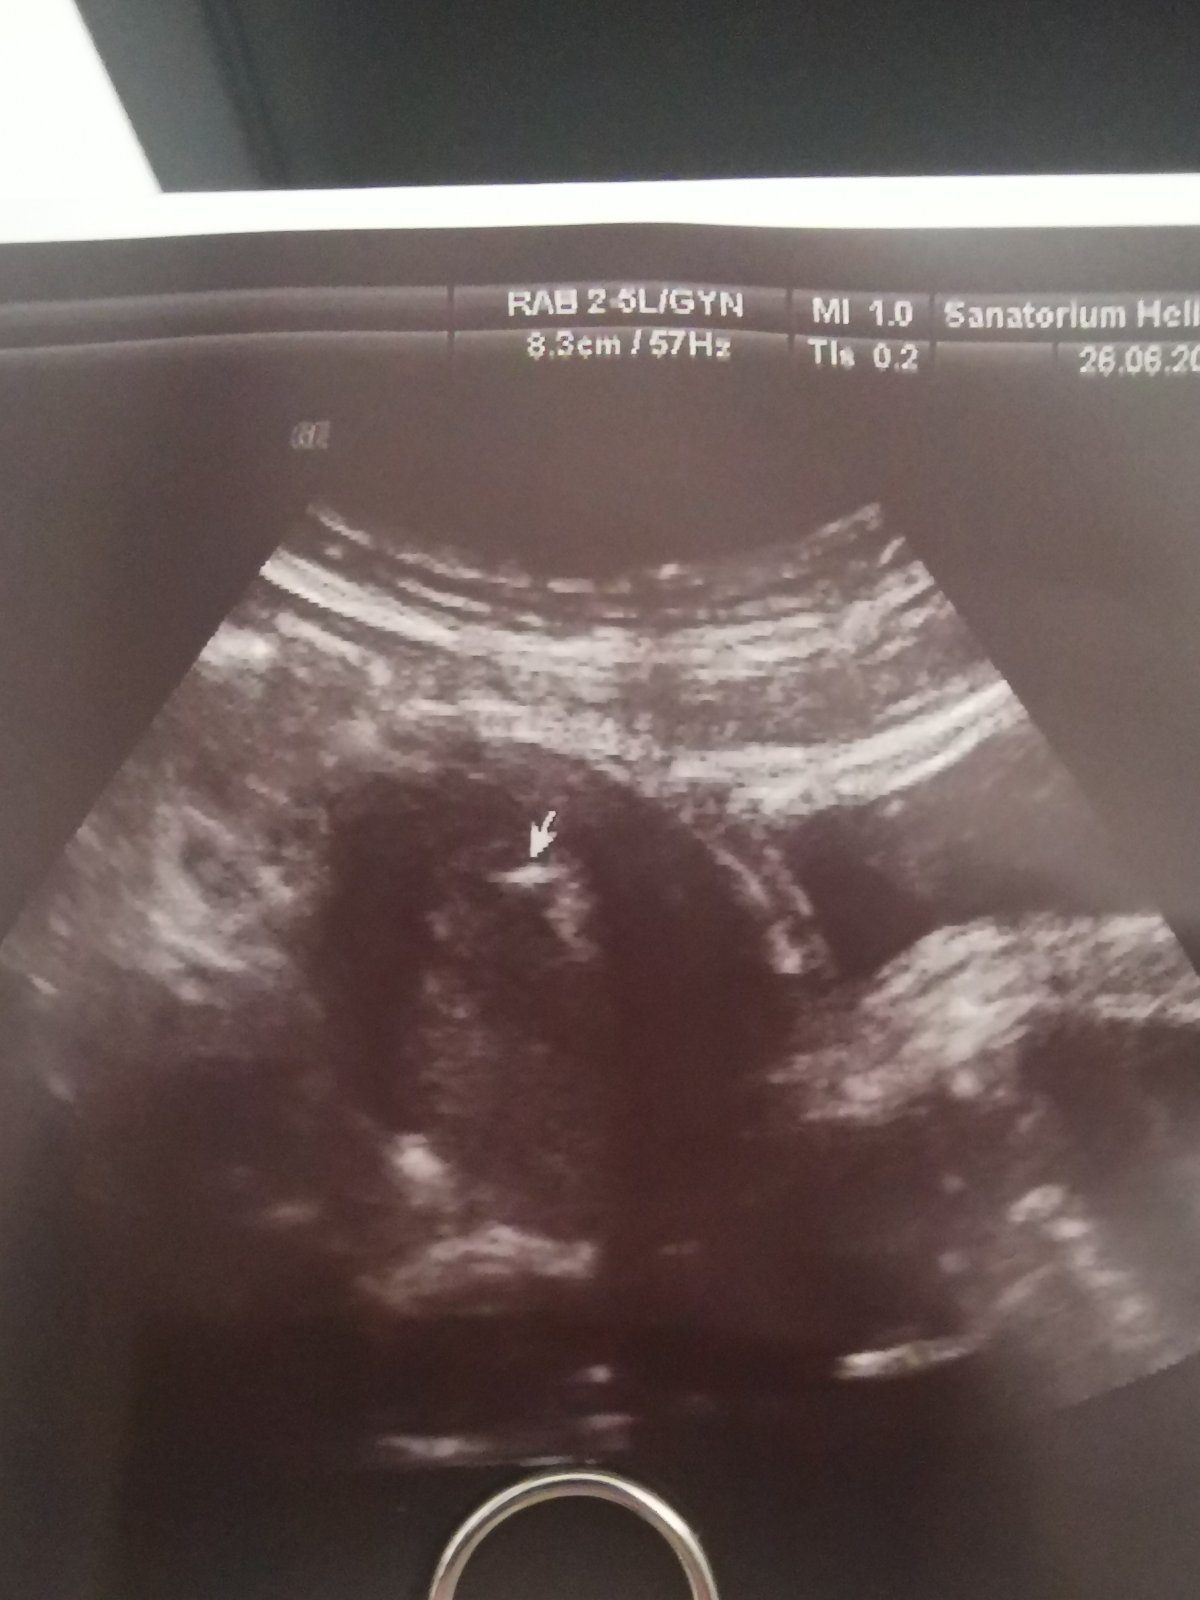

KET 26.6.2023

Ahojte, mate niektora vklad 26.6.2023? Bude to nas 7 vklad...

@lechmanova nech nam dobre dobadne... moj to bude 7 v poradi a 8 embryom..tak snad 7 je moje stastne cislo..drzim palce..

Ahojte, dnes má čaká 3.vklad tentoraz máme embrya s darovanými spermiami. Uvidíme čo to prinesie. 🤞